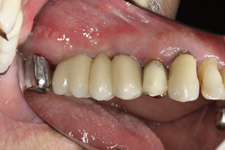

Protetické řešení může být pomocí můstku, který je kotvený na implantátech nebo pomocí jednotlivých korunek na implantátech.

V zásadě je možné do těchto můstků zařadit i přirozené zuby, zejména pokud je potřeba tyto zuby ošetřit proteticky – korunkami. Korunky nebo můstky mohou být na implantáty nacementovány nebo přišroubovány.

Zdravé zuby zůstanou zachovány a přitom náhrady jsou pevné, jako na vlastních zubech